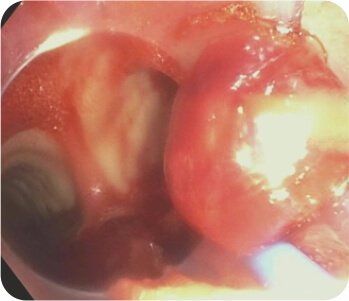

CT chest was suggestive of cavity in left upper lobe. FOB was suggestive of pus oozing from left upper lobe bronchus with a clot mass adherent to left upper lobe bronchus. Subsequent bronchoalveolar lavage was predominantly neutrophilic. Staining and culture for pyogenic, fungus, tuberculosis and nocardia was negative. Cytology was negative for malignancy. A diagnosis of Invasive Mucormycosis was made.

Rigid bronchoscopy + Cryobiopsy of protruding mass + Endobronchial blocker ( Fogarty balloon) was done.

Bronchoscopy – Mass/ Clot occluding the left upper lobe bronchus

Cryobiopsy of the protruding mass suggestive of invasive mucor mycosis (Broad aseptate hyphae)